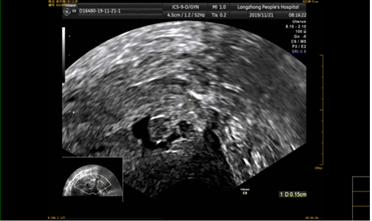

该患者孕囊位于子宫切口处肌壁内,且该处肌层菲薄,厚约3.75px(如图1,2,3)。出血风险及子宫穿孔风险极大。为了保留生育功能,确保患者生命安全,我院妇科积极发起多学科联合诊疗(MDT)会议,特邀请放射科、麻醉科、超声科等相关科室开展讨论,一致决定先由放射科行子宫动脉栓塞术并灌注甲氨蝶呤杀胚治疗(微创介入),72小时之内再行清宫术。最终,该患者在放射科顺利完成甲氨蝶呤灌注和双侧子宫动脉栓塞(如图4-5)的情况下,第二天由妇科在超声科床旁监护下成功完成清宫术(如图6),宫腔镜检查宫腔及切口处无异常。术中出血仅有5ml(出血量较常规清宫术明显减少),并于术后第三天康复出院。

图1:切口妊娠-孕囊与肌层关系